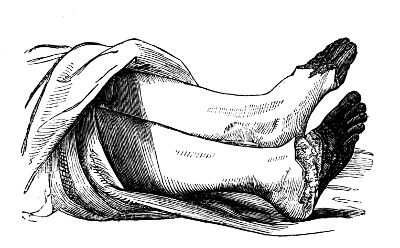

| Termination of Mortification | 43 |

| Erysipelas | 55 |